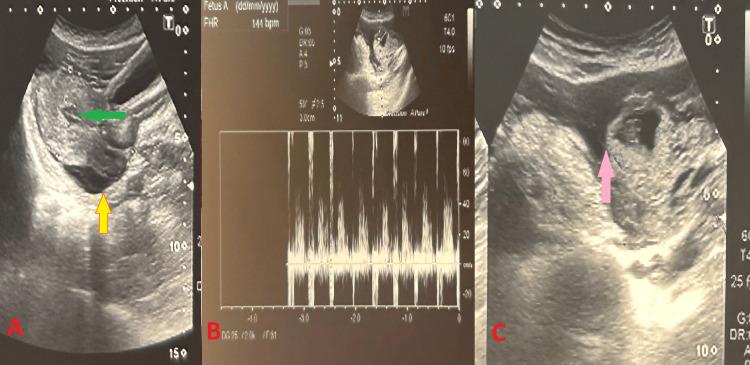

An Uncommon Presentation of a Ruptured Tubal Ectopic Pregnancy With Broad Ligament Hematoma.

Broad ligament hematomas are rare in obstetrics. These hematomas typically result from vaginal, cervical, or uterine tears that extend to the uterine or vaginal arteries. Although cases of intestinal ectopic pregnancies presenting as broad ligament hematomas with no intraperitoneal collection have been reported, no cases involving broad ligament hematomas along with hemoperitoneum following ampullary ruptured ectopic pregnancy have been documented. Internal iliac artery ligation (IIAL) is particularly useful in broad ligament hematomas. So, we present a case of ruptured ampullary ectopic pregnancy with both intraperitoneal collection and broad ligament hematoma managed by salpingectomy and bilateral IIAL.